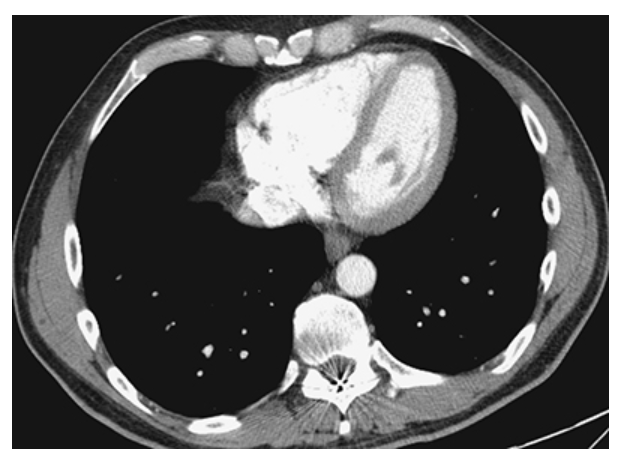

Pericardial Effusion. Contrast-enhanced CT (CECT) shows increased fluid density around the heart consistent with a pericardial effusion.

Pericardial Effusion. Normal for comparison.